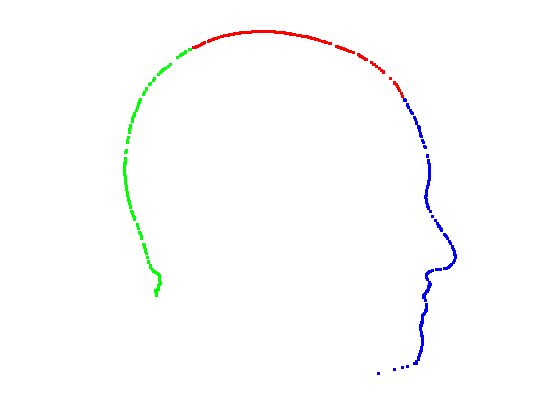

In order to find the facial contour we implemented a piecewise ICP process across the glocal symmetry plane. Each head is first rotated such that its global symmetry plane is coincident with the Y-Z plane. The facial region, as defined by the sparse model fit is then divided into a set of horizontal strips (we use 20mm steps between the nasion and pognion) in the dimension, with the back of the head being cropped out. We apply our trimmed ICP algorithm to each separate strip, so that a local symmetry plane is found for each strip and the facial contour is found by intersecting this sequence of local symmetry planes with its corresponding facial strip. For each strip (index ), we use the strip below and the strip above in the trimmed ICP process in order to reduce the sensitivity of the local symmetry planes to noise. This process is only applied to the face and the cranial region is dealt with as a whole. This is because, in strips, it does not provide sufficient constraints for ICP to lock onto and the two surfaces can slide over each other freely. Fig. 12 shows facial local symmetry contours deviating from the global symmetry plane. Points on the head profile are then extracted by detecting mesh arcs that cross a symmetry plane and linearly interpolating to extract 3D vertices that lie on that symmetry plane.

|

|

|

|